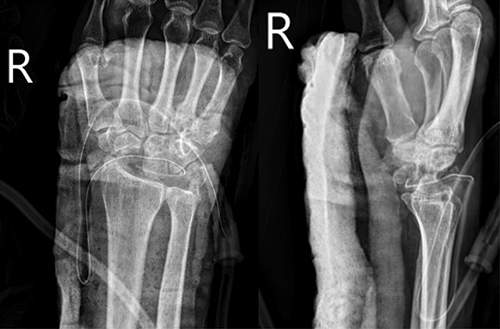

Associated Factors of Long-Term Severe Hypocalcemia after Total Parathyroidectomy with Forearm Auto-Transplantation in Patients with Renal Hyperparathyroidism

Potchara Rungprasertsuk, MD¹, Sasithorn Sujarittanakarn, MD¹, Wilairat Thoviriyavej, MD¹

380